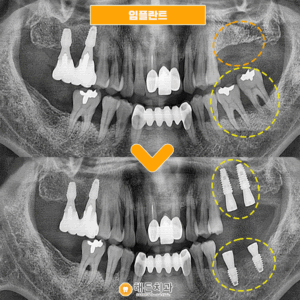

임플란트 환자분의 간식선물🍩

안녕하세요~ 해든치과입니다🤭   해든치과에는 가족단위의 환자분들이 굉장히 많으신데요!   임플란트 치료를 마무리하신 환자분께서 치료 잘 해주셔서 감사하시다며 다음에 올때 꼭 빵 사다주신다고 하셔서 빈손으로 오셔도 괜찮으니 그냥 오시라고 말씀드렸었는데       어머님 진료예약에 같이 내원해주시는길에 간식을 사다주셨습니다😭       항상 생각해주셔서 감사합니다 맛있게 먹고 힘내서 즐겁게 더보기…